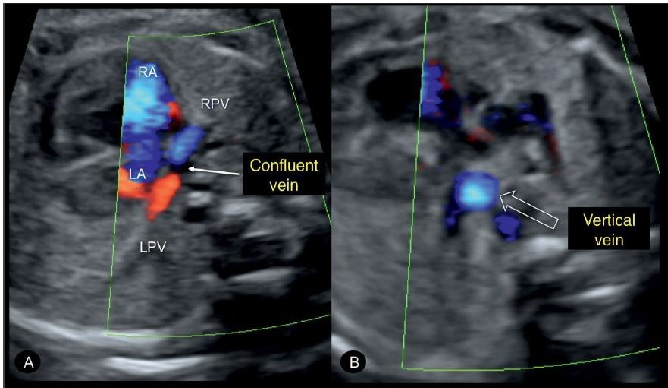

Hình 8: (A) Hình ảnh Doppler màu mặt cắt ngang ngực thai thi có bất thường hồi lưu tĩnh mạch phổi toàn phần (TAPVR). Chú ý tĩnh mạch phổi phải (RPV) và tĩnh mạch phổi trái (LPV) không đổ vào nhĩ trái mà đổ vào tĩnh mạch thu thập (confluent vein), ngăn cách với nhĩ trái bởi một dải mỏng. (B) Tịnh tiến đầu dò về phía đầu thai nhi thấy hình ảnh mặt cắt ngang tĩnh mạnh đứng dọc (vertical vein) ở trong lồng ngực (mũi tên rỗng).